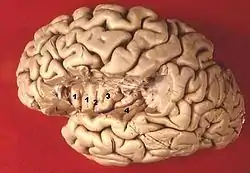

![]() Section of brain showing upper surface of temporal lobe ("transverse temporal gyri" visible at center left) | |